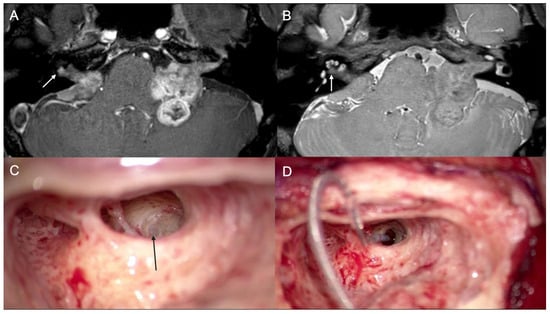

3.2. Case 2